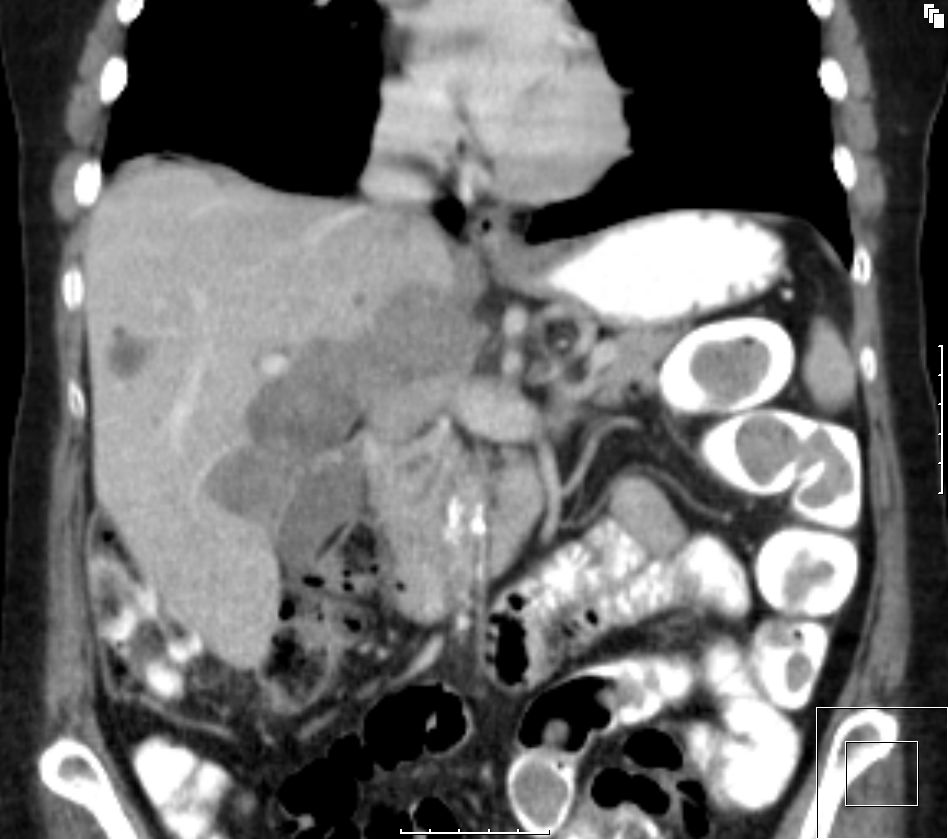

Rezidiv eines serösen Ovarialkarzinoms. Großer Tumor im Leberhilus, intrahepatische Herde. |

Pfortader frei. | |||